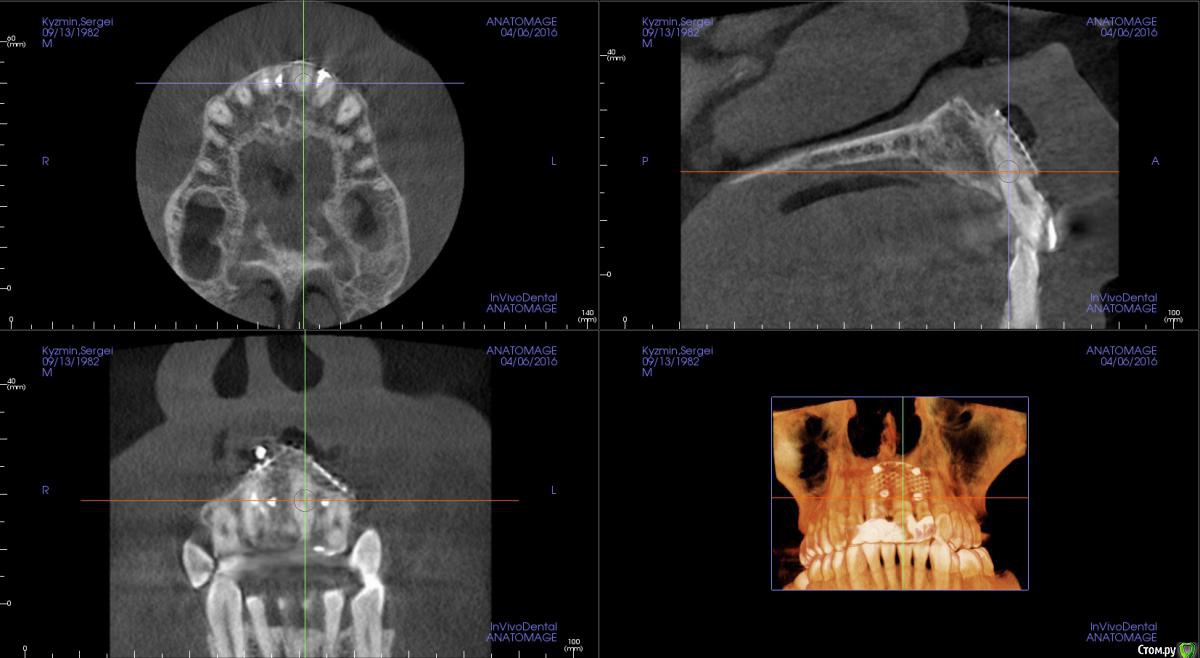

kamranchick Опубликовано 17 апреля, 2016 Поделиться Опубликовано 17 апреля, 2016 Пришел пациентДок привет, что то зуб шатается, можно ли его оставить, вот такие дела)как бы вы поступили бы? Ссылка на комментарий

dantist_movani Опубликовано 27 апреля, 2016 Поделиться Опубликовано 27 апреля, 2016 Пришел пациентДок привет, что то зуб шатается, можно ли его оставить, вот такие дела)как бы вы поступили бы?1)проверил бы на витальность2)Репозиция и шинирование орто ретейнером с жидкотекучим композитомпохожая ситуация была год назад, правда отлом кортикалки не столь значительный был. Ретейнер снял через 6 мес, все Ок, зуб не почернел♿, эод -8 в дуге, пац очень доволен Ссылка на комментарий